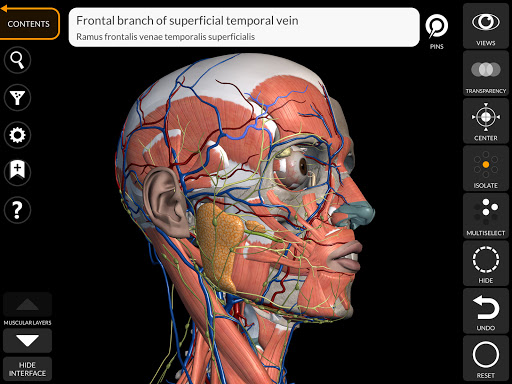

"Anatomía - Atlas 3D" permite estudiar la anatomía humana de forma fácil e interactiva.

A través de una interfaz sencilla e intuitiva es posible observar cada estructura anatómica desde cualquier ángulo.

Los modelos anatómicos 3D son especialmente detallados y con texturas de hasta una resolución de 4k.

La subdivisión por regiones y las vistas predefinidas facilitan la observación y el estudio de partes individuales o grupos de sistemas y las relaciones entre los diferentes órganos.

nervioso • Sistema respiratorio • Sistema digestivo • Sistema urogenital (masculino y femenino) • Sistema endocrino • Sistema linfático • Sistema ocular y auditivo CARACTERÍSTICAS • Interfaz sencilla e intuitiva • Rotar y hacer zoom en cada modelo en el espacio 3D • Opción para ocultar o aislar uno o varios modelos seleccionados • Filtro para ocultar o mostrar cada sistema • Función de búsqueda para encontrar fácilmente cada parte anatómica • Función de marcador para guardar vistas personalizadas • Rotación inteligente que mueve el centro de rotación automáticamente • Función de transparencia • Visualización de músculos a través de niveles de capas desde las superficiales hasta las más profundas • Al seleccionar un modelo o un pin, aparece el término anatómico relacionado • Descripción de los músculos: origen, inserción, inervación y acción • Mostrar/ocultar interfaz de usuario (muy útil con pantallas pequeñas) MULTILINGÜE • Los términos anatómicos y la interfaz de usuario están disponibles en 11 idiomas: latín, inglés, francés, alemán, italiano, portugués, turco, ruso, español, Chino, japonés y coreano • Los términos anatómicos se pueden mostrar en dos idiomas simultáneamente REQUISITOS DEL SISTEMA • Android 8.0 o posterior, dispositivos con al menos 3 GB de RAM Reversi